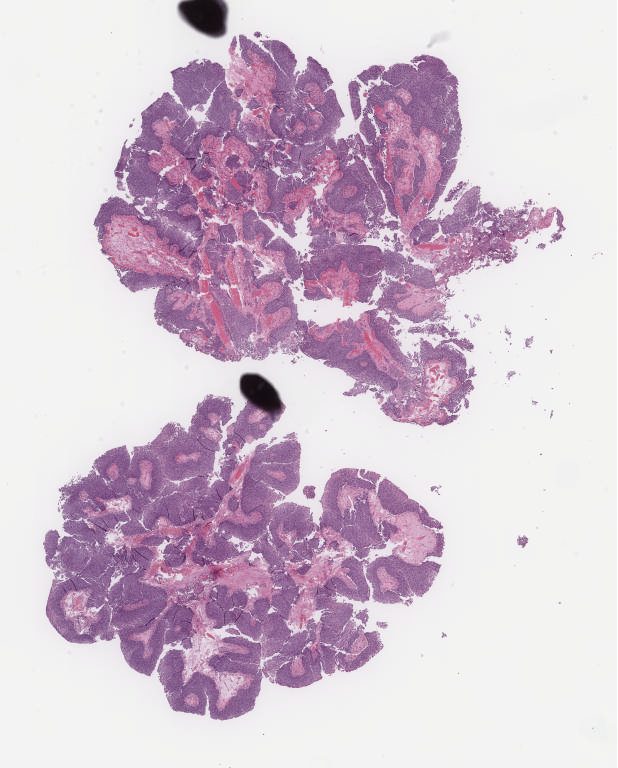

Case3.svs

40652

x

43494

@

40X